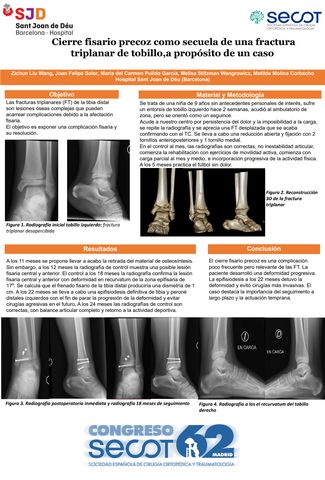

Cierre fisario precoz como secuela de una fractura triplanar de tobillo, a propósito de un caso

ZICHUN LIU WANG, JOAN FELIPE SOLER, MARIA DEL CARMEN PULIDO GARCIA, MELISA STITZMAN WENGROWICZ, MATILDE MOLINA CORBACHO